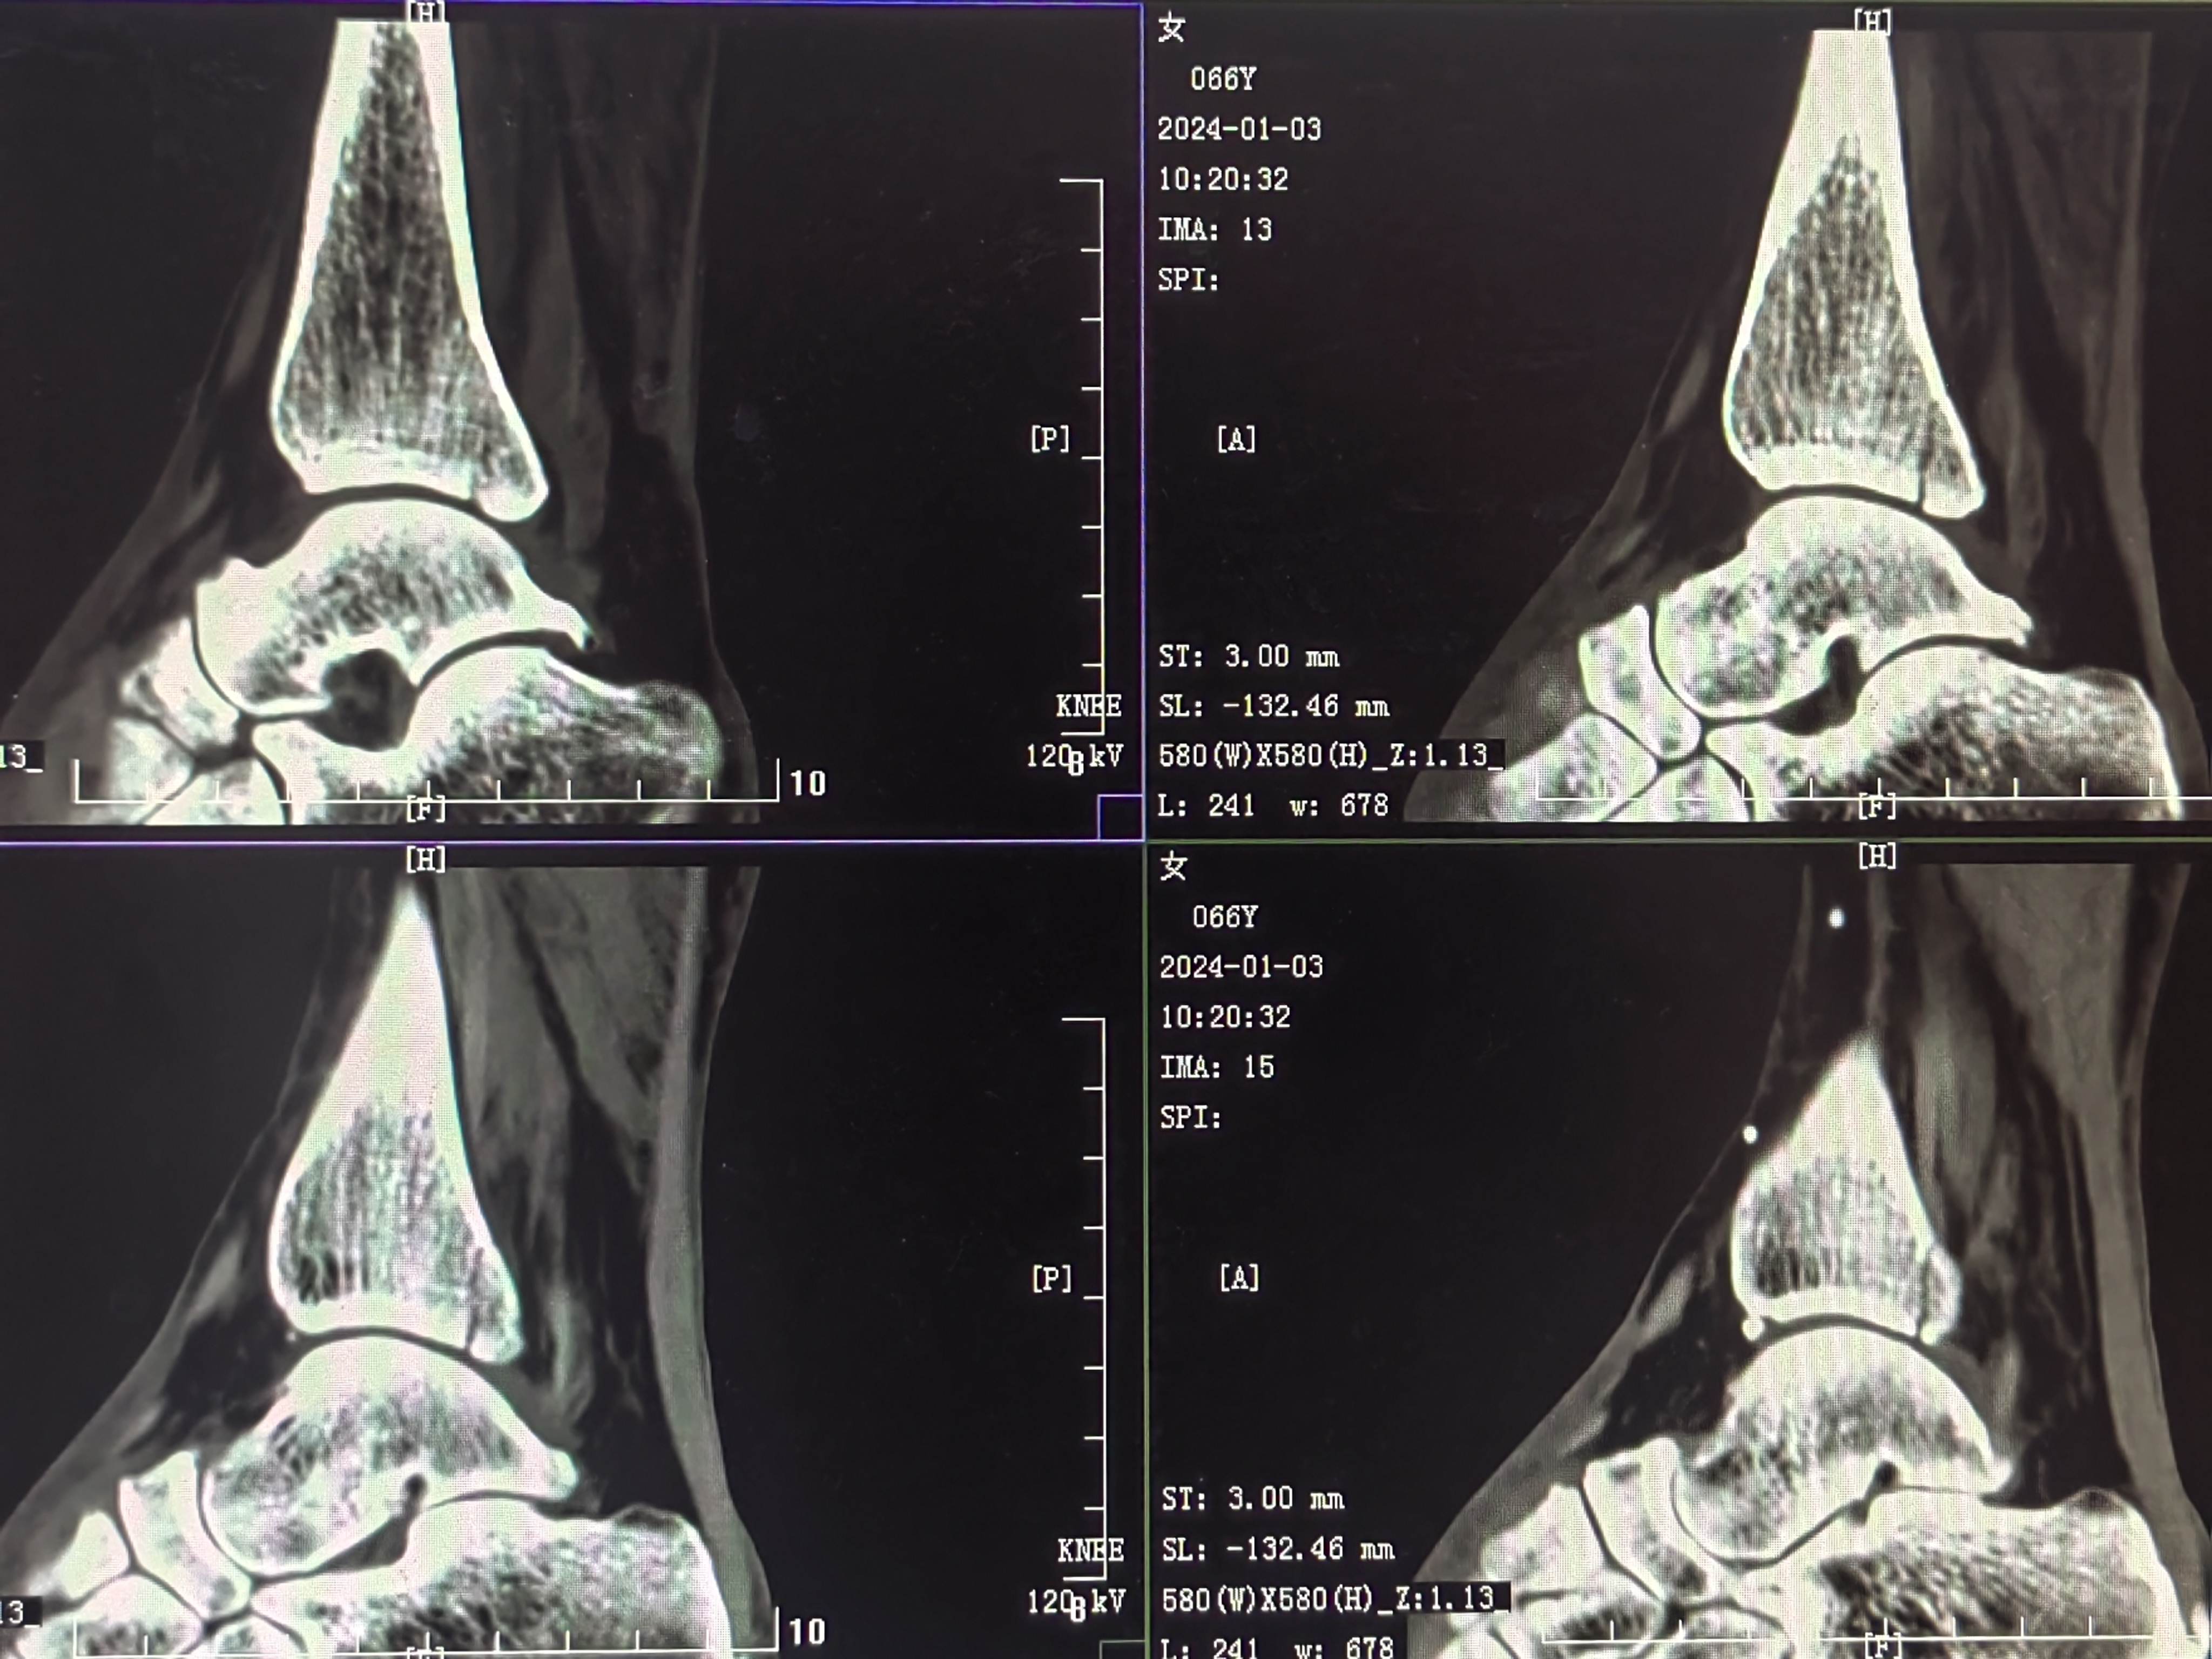

患者矫,女,66岁,左踝扭伤肿痛畸形2小时

初步诊断:左踝关节骨折(L-H分型:旋后外旋型IV)

CT